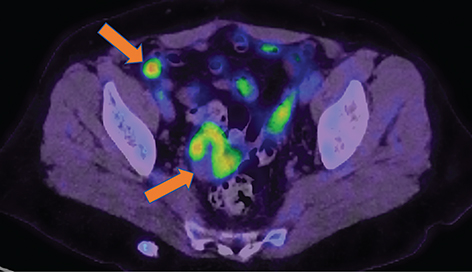

18F-FDG PET using EORTC or PERCIST criteria is useful in detecting early tumour response and precedes tumour markers response by 1 month and can also predict second-look surgery outcome and survival (31). FDG PET can predict the outcome after the first cycle of neoadjuvant chemotherapy early, a decrease of >20% in SUVmax after the first cycle of chemotherapy and >55% after the third cycle were found to correlate significantly with overall survival (32). FDG PET CT is superior to morphological imaging in assessing treatment response as molecular imaging with FDG PET identifies residual viable tumour whereas inflammatory lymph nodes or scar tissue may be misinterpreted as residual disease on morphological imaging (Figure 1).

Fig 1

Figure 1. Treatment response evaluation. 18F-FDG PET/CT images obtained from a 68-yr-old patient with recurrent ovarian carcinoma for assessment of treatment response. Image A demonstrates an intensely FDG-avid metastatic abdominal mass on pre-treatment FDG PET/CT, with significant post-treatment improvement noted on Image B.